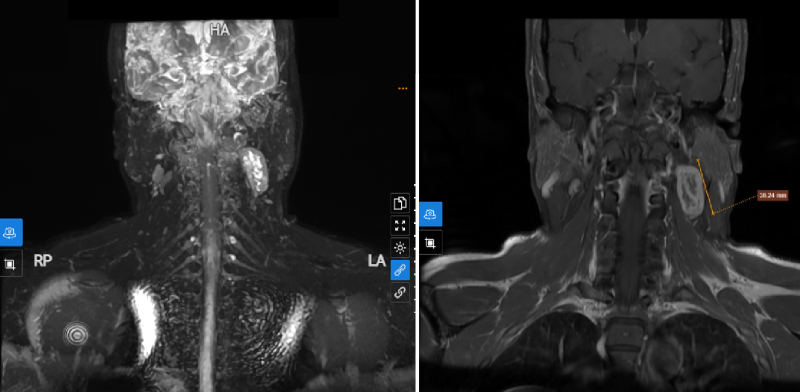

Bệnh nhân có tiền sử mắc ung thư buồng trứng đã phẫu thuật. Trên siêu âm phần mềm phát hiện hình ảnh khối tổ chức vùng cổ trái, nghi ngờ có nguồn gốc từ rễ thần kinh. Ngay lập tức, bệnh nhân được chỉ định thực hiện chụp MRI vùng cổ. Kết quả phát hiện hình ảnh thoát vị đĩa đệm cột sống cổ C4/5, C5/6, C6/7 thể trung tâm, không chèn ép tủy và rễ thần kinh. Đáng chú ý, trên phim chụp phát hiện tổn thương dạng đặc phần mềm vùng góc hàm trái, hướng đến nguồn gốc thần kinh, nghi ngờ liên quan đến nhánh thần kinh C2-3 cổ trái. Bệnh nhân được sinh thiết dưới hướng dẫn của siêu âm đánh giá mô bệnh học, cho kết quả chẩn đoán xác định đó là theo dõi u tế bào Schwannoma.

Tổn thương phát hiện trên phim chụp MRI vùng cổ